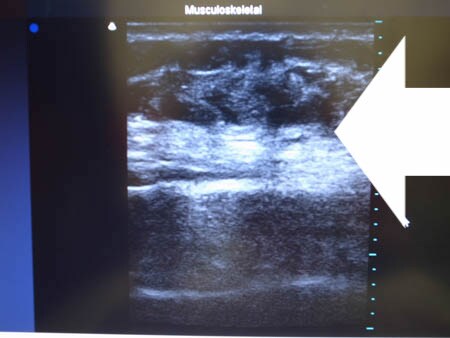

いつものように3Dタッチビュー(超音波)で

皮下脂肪層を評価してみましょう。

上腹部